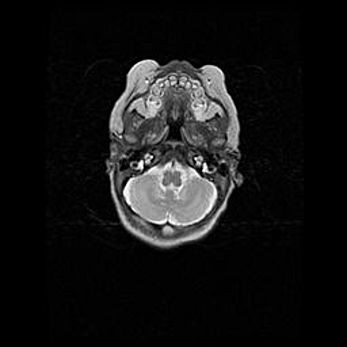

Лейкомаляция с кистозно-глиозной дегенерацией головного мозга.

Возраст: 2 месяца 25 дней

Вес: 6400 г

Окружность головы: 40 см

Срок гестации: 41 неделя

Лейкомаляцию относят к ишемически-гипоксическим повреждениям головного мозга, диагностируемым у новорожденных. При лейкомаляции в головном мозге обнаруживают очаги некроза, возникшие после тяжелой гипоксии и нарушения кровотока. В процессе морфогенеза очаги проходят три стадии: 1) развития некроза, 2) резорбции и 3) формирования глиозного рубца или кисты. Перивентрикулярная лейкомаляция (ПЛ) встречается примерно в 12% случаев среди новорожденных, обычно – у недоношенных детей, причем, частота ее зависит от массы, с которой младенец появился на свет. Наибольшее число малышей страдает лейкомаляцией, если масса при рождении 1500-2500 г.